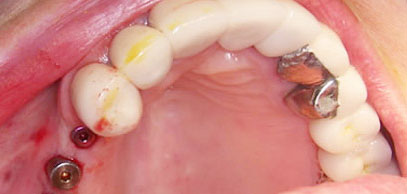

Ngược lại, khi bạn đến gặp BS để yêu cầu ghép Implant, vùng cần ghép Implant thường ở trong trạng thái bình thường và khỏe mạnh: không tồn tại nhiễm trùng vì răng đã được nhổ và lành thương từ lâu, không có sưng viêm, do vậy sẽ đáp ứng rất tốt với thuốc tê và các loại thuốc giảm đau khác. Ngoài ra, mạch máu và thần kinh tại vùng này cũng đã bị tiêu đi ít nhiều trong thời gian dài bị mất răng, do đó vùng này cũng ít nhạy cảm với đau hơn.

Hình: cấy ghép Implant trước và sau khi phẫu thuật. Vì khi mất răng, mạch máu và thần kinh tại nơi đó sẽ bị tiêu đi, nên việc cấy ghép Implant sẽ ít “nhạy cảm” và cũng ít chảy máu hơn so với khi nhổ răng.

Trong trường hợp bạn nhổ răng kết hợp với cấy ghép Implant trong 1 lần phẫu thuật, trụ Implant sẽ đóng vai trò như một phần của cơ thể bạn trong ổ răng sau khi nhổ, nên thời gian lành thương sẽ nhanh hơn và cũng dễ dàng hơn, vì bình thường thì cơ thể phải tái tạo lại toàn bộ xương bị mất đi khi nhổ răng nên sẽ lâu lành thương hơn.